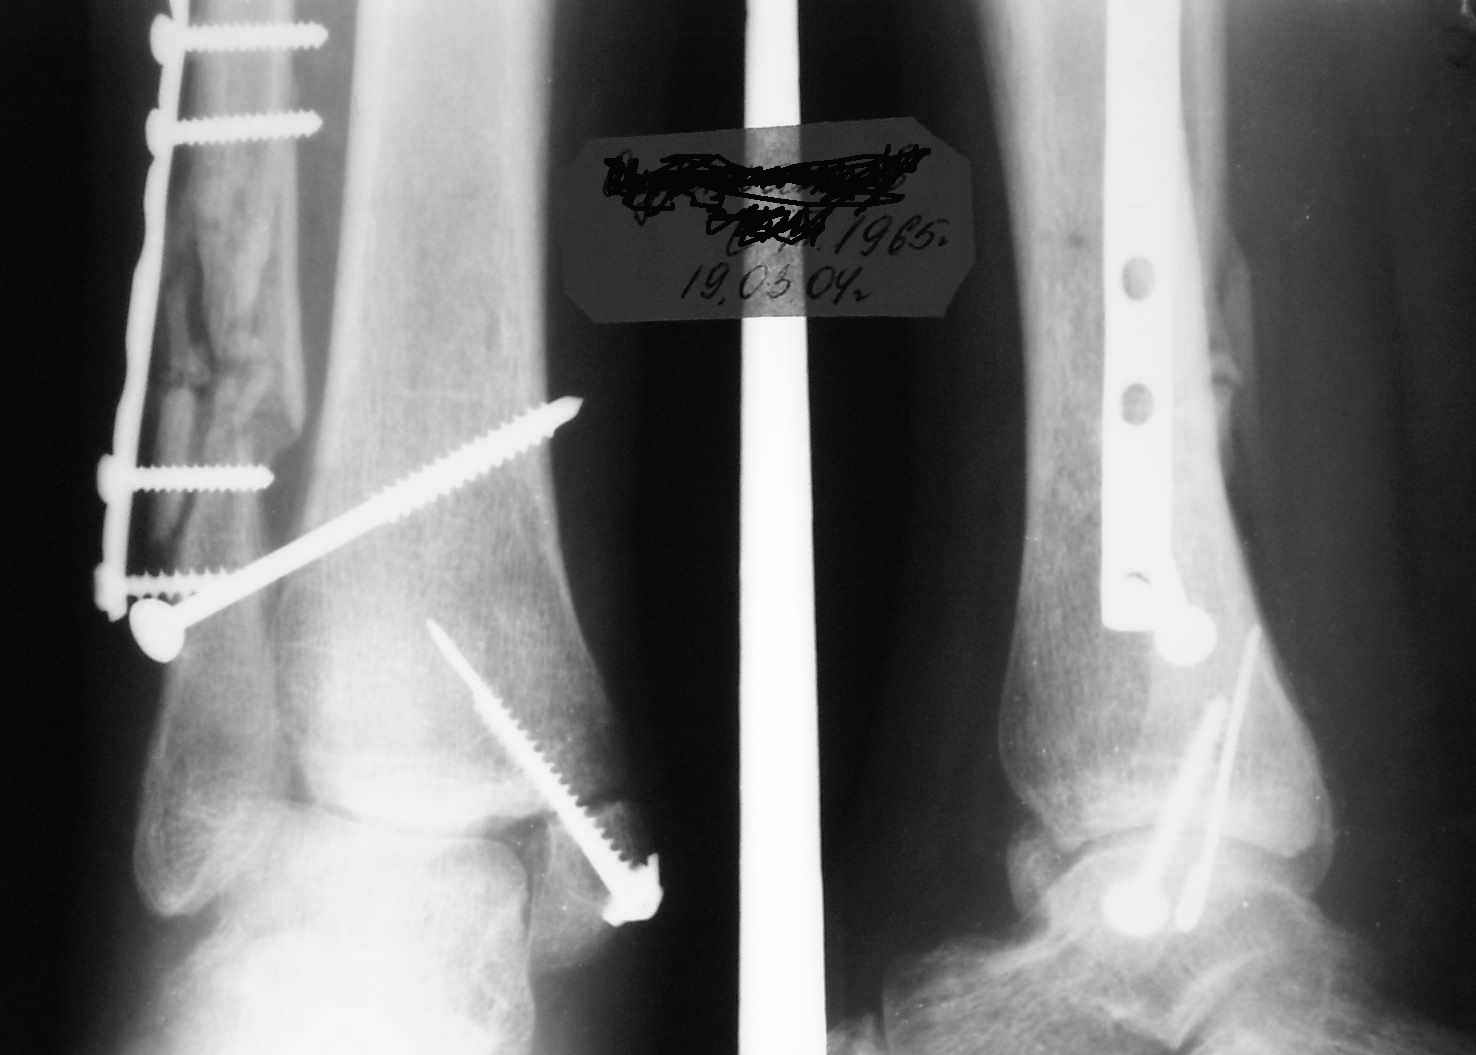

Ниже рентгенограммы

До операции 28 июля

Операция 29 июля

Через месяц

Боковой через месяц

15 ноября прямой

15 ноября боковой

15 ноября трехчетвертной

12 января прямой

12 января боковой

12 января трехчетвертной

Риторический вопрос - в каком руководстве рекомендован такой способ остеосинтеза наружной лодыжки?

Очевидно, такой результат операции был запрограммирован. При невосстановленной длине и практически нефиксированной малоберцовой кости (этот кортикальный винт - как карандаш в стакане), при неустраненном подвывихе, невправленной и тоже нефиксированной внутренней лодыжке нет стабильной вилки сустава. Если такую операцию сделать даже сразу, а не через 4 месяца, то результат ожидаем

тот же.

Вообще говоря, такое повреждение вполне успешно можно лечить без операции - если 6 недель подержать в гипсовом "сапожке" с хорошо устраненным подвывихом. Вероятное несращение внутренней лодыжки не обязательно компрометирует результат.

Ну а уж если выбран остеосинтез - нначать надо было с репозиции малоберцовой кости с точным восстановлением длины, с фиксацией треть-трубчатой пластиной по задней поверхности. Позиционный винт

избыточен - повреждение практически подсиндесмозное. А если бы

действительно было повреждение синдесмоза - в 4 месяца позиционный винт - не решение. Внутренню лодыжку такую - надо было бы спицами и проволочной петлей. Извините за эти банальности.

Вариант с артродезом уже обсудили. Хотя, после увиденых снимков, пессимизм насчет восстановительной операции у меня, например, несколько уменьшился. Особенного уж какого-то остеопороза не видно даже на январских снимках. Можно черед мини-доступы убрать винты, аппаратом вправить малоберцовую кость, устранить подвывих стопы. Ну а дальше фиксировать малоберцовую пластиной сзади. А может, и напряженной Y-спицей попробовать - Анатолий Федорович, как Вы полагаете? Внутреннюю - то, что осталось, если уже не получится сделать спицами и проволокой, то что-то типа пластики дельтовидной связки. А может, и не трогать ее вовсе... В общем, выбор непростой,

много факторов надо взвесить.

Если до сих ничего не сделано, с артродезом сустава в данный момент я бы повременил, на выставленных январских снимках хорошо сохранившийся сустав, а в "мортиз" (трехчетвертной) и на боковых снимках не менее 5 мм укорочение малоберцовой кости. Косые переломы лучше фиксировать пластинами, как то мы разбирали случай, где было отмечено, что это закон "таранная кость всегда следует за малоберцовой".

В данном случаи я бы уговорил больного на реконструкцию, для этого после удаления шурупов, спереди очистить от рубцов синдесмоз, несросшуюся наружную лодыжку - остеотомия по линии перелома и компрессирующий (lagging technique) кортикальный шуруп 3.5 мм по поперечнику остеотомии. Следующий этап - восстановление длины малоберцовой за счет удлинения, сделать поперечную остеотомию где-то на уровне сантиметр выше вашего синдесмозного шурупа, наложить длинную пластинку, прикрепить пластину за дистальный конец двумя или тремя шурупами; сохраняя контакт пластины с костью, имеющимся

compression&tension device AO system (при отсутствии любой lamina spreader подойдет, создать дистанцию между пластиной и шурупом, проведенным проксимальнее пластины) толкая проксимальный отдел пластины, низвести пластину, мортиз рентгенограмма подскажет на сколько. Если заранее сделать предоперационный план (ренгенограмма другой стороны), тогда точно можно определить, на сколько вам необходимо сделать поперечную остеотомию малоберцовой кости, для закрытия создавшегося дефекта.